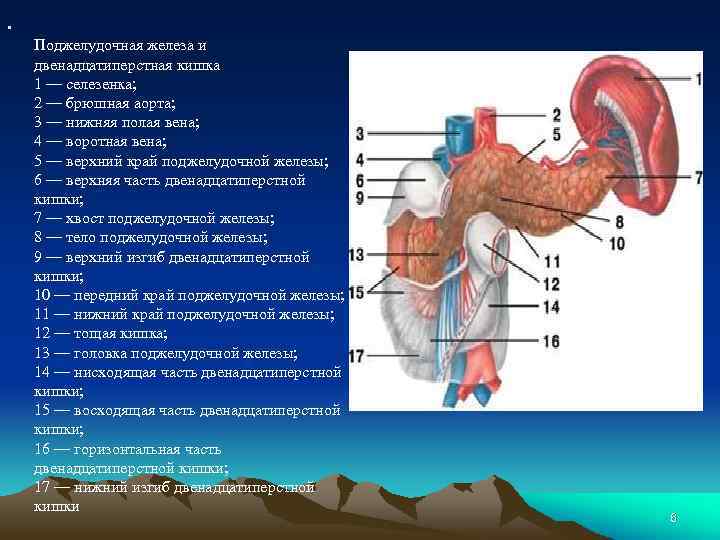

• Поджелудочная железа и двенадцатиперстная кишка 1 — селезенка; 2 — брюшная аорта; 3 — нижняя полая вена; 4 — воротная вена; 5 — верхний край поджелудочной железы; 6 — верхняя часть двенадцатиперстной кишки; 7 — хвост поджелудочной железы; 8 — тело поджелудочной железы; 9 — верхний изгиб двенадцатиперстной кишки; 10 — передний край поджелудочной железы; 11 — нижний край поджелудочной железы; 12 — тощая кишка; 13 — головка поджелудочной железы; 14 — нисходящая часть двенадцатиперстной кишки; 15 — восходящая часть двенадцатиперстной кишки; 16 — горизонтальная часть двенадцатиперстной кишки; 17 — нижний изгиб двенадцатиперстной кишки 6